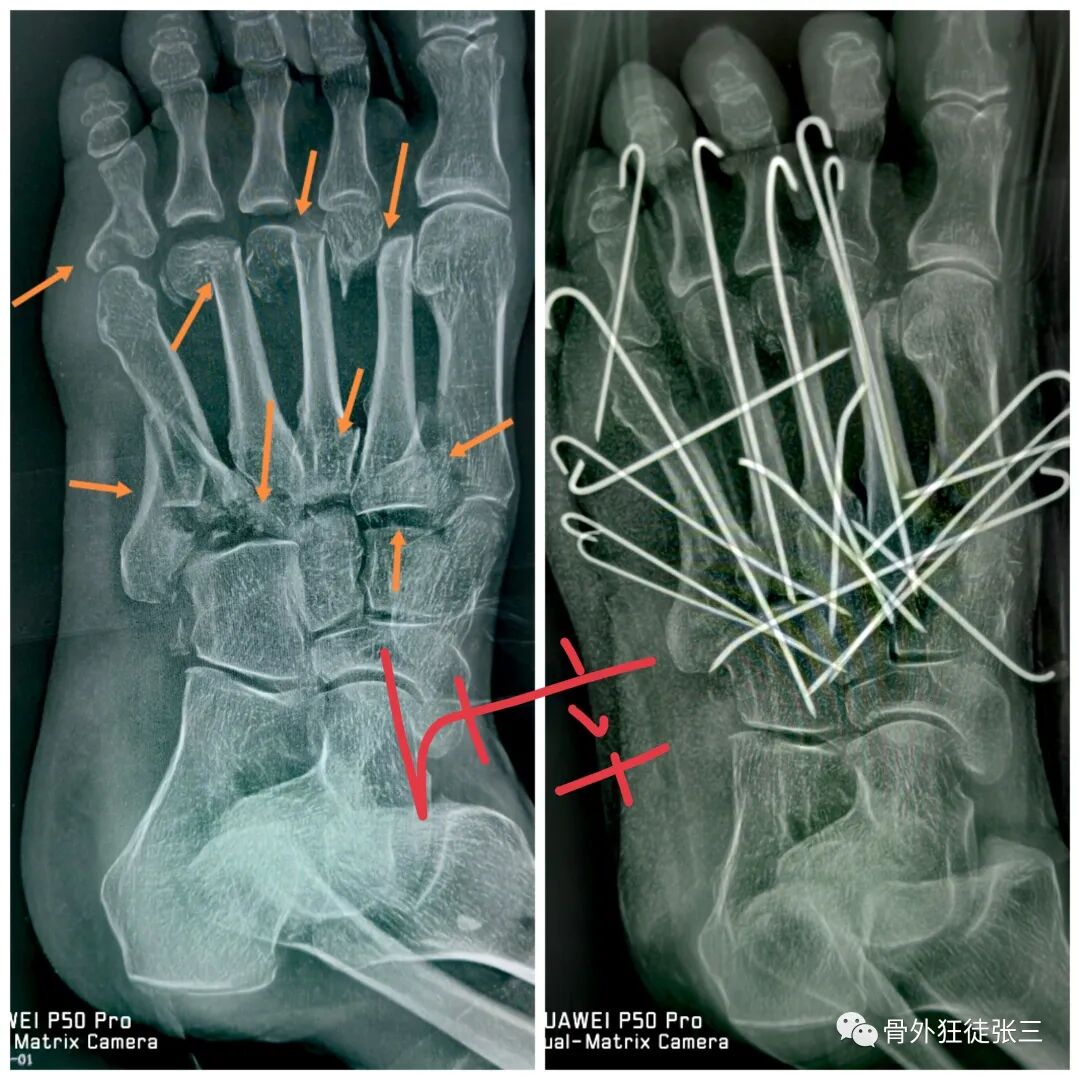

病例8,第234跖骨骨折,闭合穿针

病例33,开放性Lisfranc损伤+第2345跖骨骨折脱位